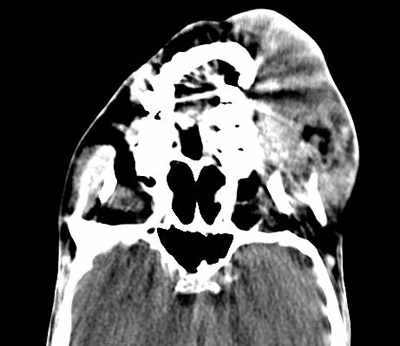

= Tomografía Axial Computarizada (TAC) del Macizo Facial. # 08-1451

En cortes craneales observamos imagen hipertensa de 34 mm en hemicara izquierda que mide 12×6 y se extienden hacia el paladar duro. No existe destrucción ósea, solo se observa deformidad de la arcada dentaria la cual aparece desplazada hacia la derecha, alcanzando fosa nasal de ese lado.

Senos maxilares normales, no invaden las órbitas.

= Tomografía Axial Computarizada (TAC) de Orbita. # 08-1515

Se observan grandes masas en región maseterina izquierda con destrucción parcial del maxilar superior izquierdo. El nervio óptico derecho ligeramente redundante. Nervio óptico izquierdo afinado sin signos de proceso tumoral infraorbitario.

Macizo Facial. # 08-1451 (ver figura 4)

Figura 4